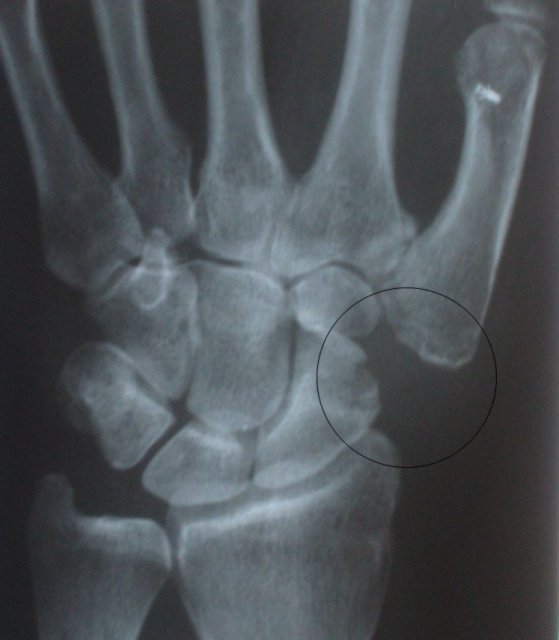

For this operation there had been no necessity for an x-ray while the pin was in place. One taken later shows the gap left by the trapezium bone's removal, the spare tendon now filling the gap being invisible to x-rays. The anchor for the volar ligament can be seen at the upper right.